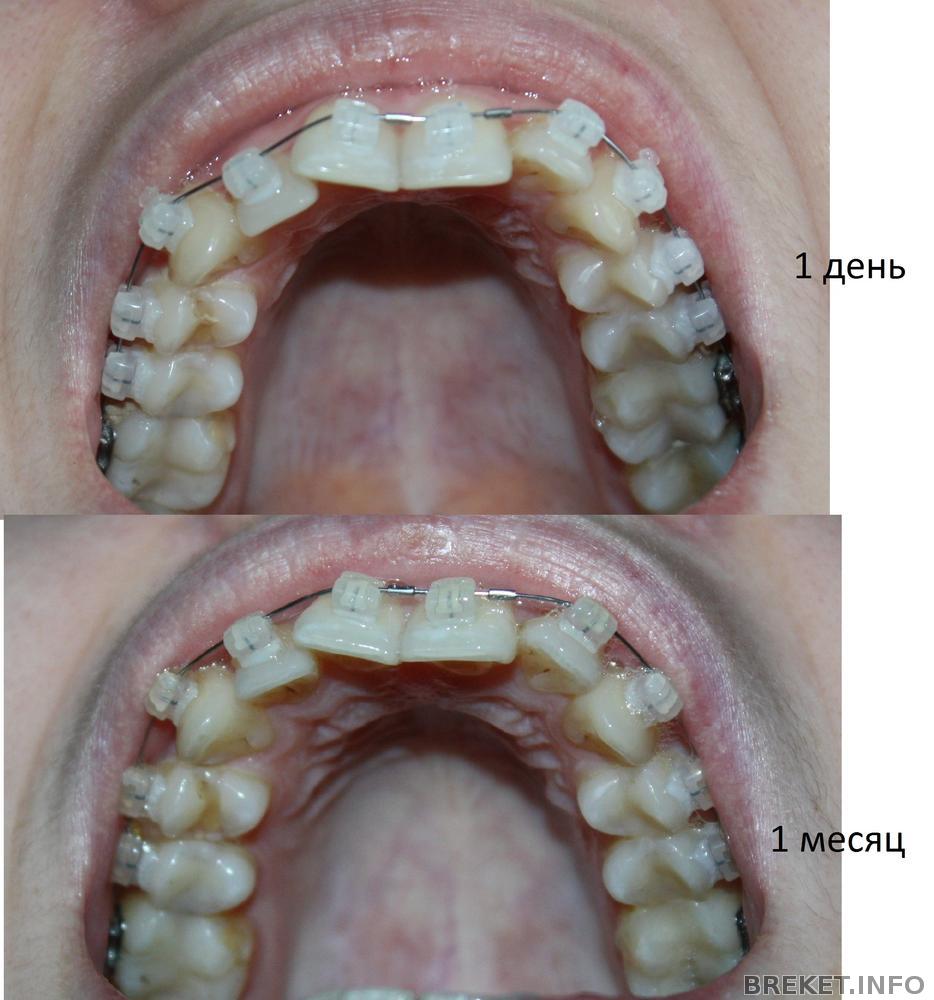

Ну очень слабое движение..(((

Я в печали... Насмотрелась тут на супер движения зубов, и ожидала такого же... да и на Даймон надежда была большая..., Вот прошел месяц, а результаты минимальны..(( Муж вообще говорит что не видит разницы...((( Хочу побыстрее к орту может он меня чем то подбодрит...(((

1den-4nedeli2.jpg